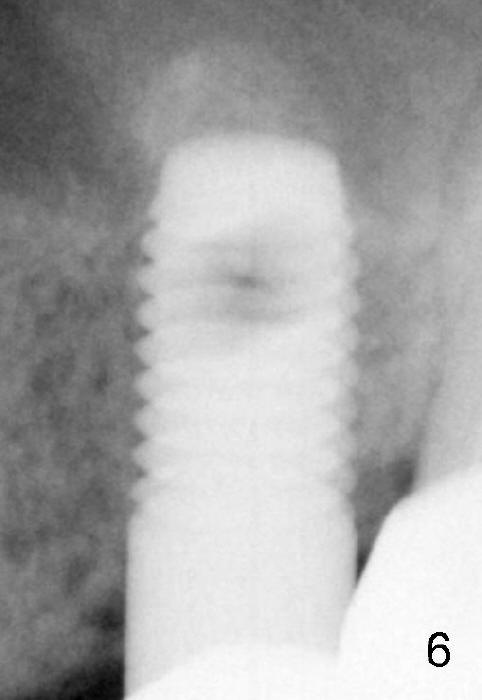

A 5x14 mm cylindrical implant (Fig.3 I) was inserted with elevation of the apparent sinus floor (>, no allograft used in case of sinus infection). Seven months postop, the density of sinus floor increases (Fig.4 <). The implant is stable and processed for crown (Fig.5 C, different view of the lifted sinus floor (<)). While sinus floor density is decreasing, the mesial and distal bone density is increasing 6 months (Fig.6), 1 year 6 months (Fig.7) and 3 year 6 months (Fig.8) post cementa-tion.